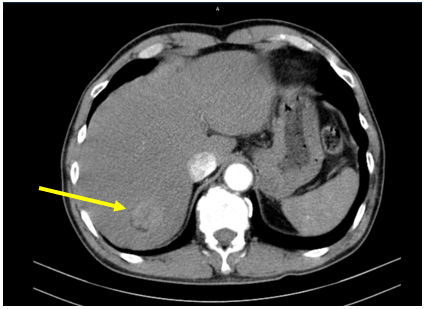

Hình 2: U gan sau SIRT (bên trái, mũi tên vàng) so với trước SIRT (bên phải, mũi tên vàng)